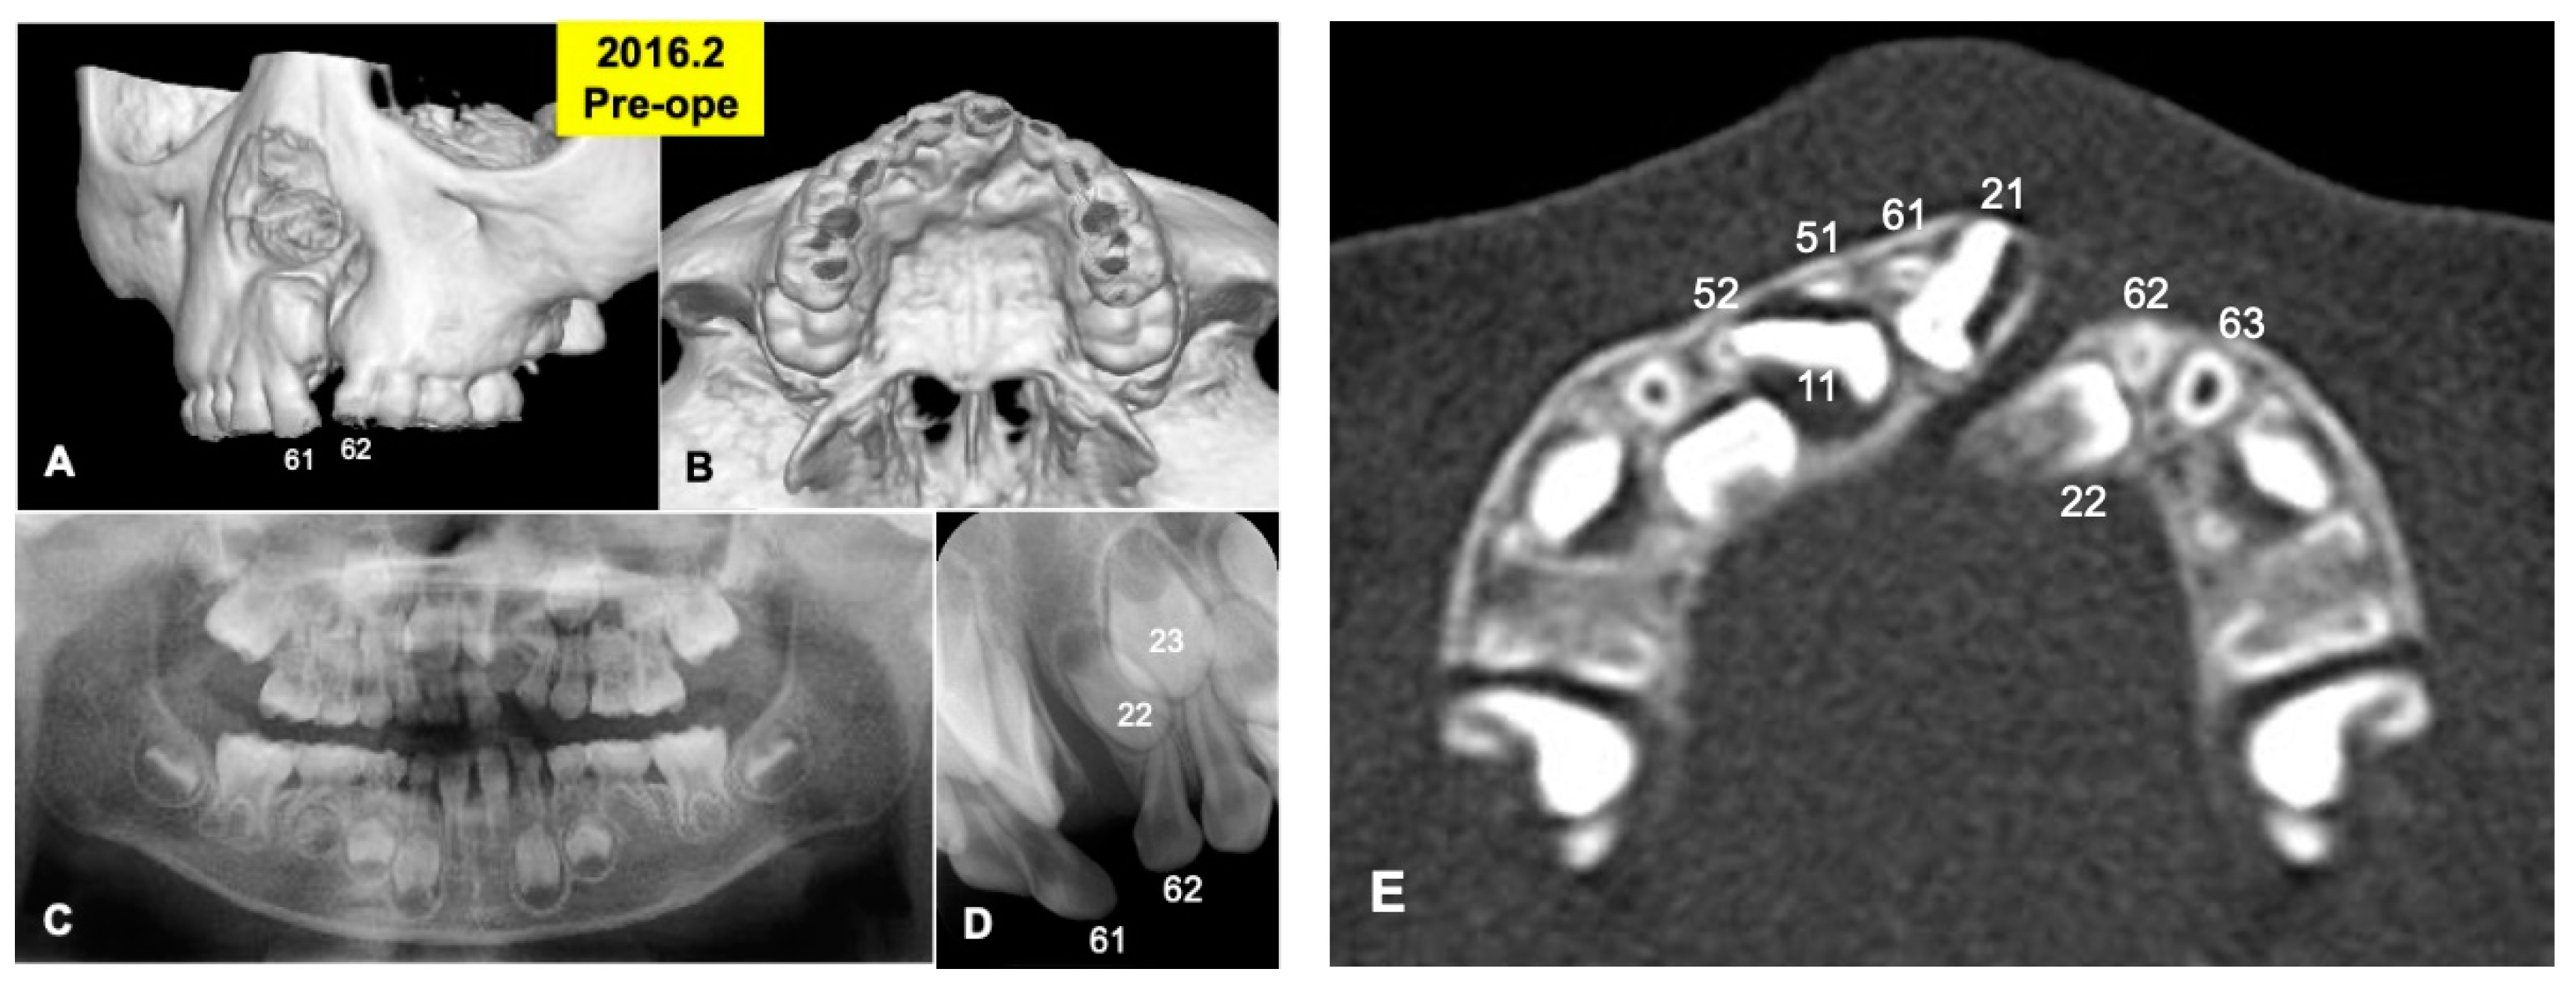

Figure 1.

X-ray photos in 2016 before surgery. (A) Labial view of 3D-CT showing unilateral alveolar cleft. (B) Palatal view of 3D-CT. (C) Panoramic view in mixed dentition stage of 6-year-old boy. Congenital missing teeth: 12,21,25. (D) Occlusal view indicating unilateral cleft between primary teeth 61 and 62 (permanent teeth 21 and 22). (E) Axial CT photo. Coronal level of cleft-adjacent incisor (21). Images of primary teeth-roots (52, 51, 61, 62) before extraction.